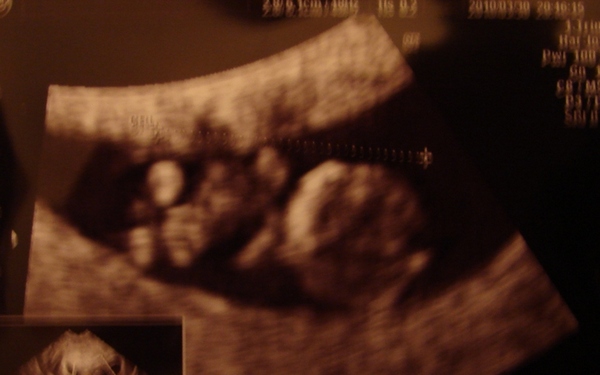

kis formás babácskánk :lol: :lol:

gratula a csini képhez! jó hogy feltetted.

Hurrá hurrá gratula a 2,4 cm-es babóhoz.

Örülök hogy szimpi a doki. Szupi. Vonalzód nagyon szuppppper.